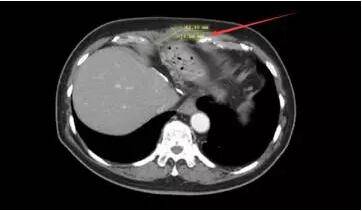

在疾病进展、索拉菲尼治疗失败后,患者及家属决定做最后一搏,尝试使用Keytruda进行治疗,剂量为2mg/kg,每3周注射一次。在6个周期后,复查CT结果发现肿块组织从8*6cm缩小到4*1.6cm,AFP从8877mcg/L降至1.7mcg/L. 效果让人非常惊讶,而且患者目前耐受Keytruda治疗,没有出现什么严重的副作用。

治疗后CT影像